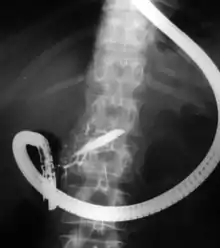

تصوير البنكرياس والأقنية الصفراوية بالتنظير الباطني بالطريق الراجع (Endoscopic retrograde cholangiopancreatography) (ERCP) هو الاسلوب الذي يجمع بين استخدام التنظير الداخلي و التنظير التألقي لتشخيص وعلاج بعض مشاكل جهاز القنوات الصفراوية و القنوات المعثكلية. من خلال المنظار يمكن للطبيب مشاهدة داخل الإثني عشر والمعدة و حقن الأصباغ في شجرة القنوات المرارية والبنكرياسية بحيث يمكن مشاهدتها بالأشعة السينية. تستخدم أساسا هذه التقنية لتشخيص وعلاج اٍصابات القناة الصفراوية[1] ، بما في ذلك الحصاة الصفراوية، الاٍتهابات (الندب)، التسريبات (من الجروح والجراحة) و السرطان. يمكن اٍستخدام هذه الطريقة لأغراض تشخيصية وعلاجية. على الرغم من تقدم تقنيات التشخيص الآمنة والغير بضعية (غير جراحية) مثل تصوير البنكرياس بالرنين المغناطيسي و التنظير الباطني فائق الصوت اٍلا أن تصوير البنكرياس بالتنظير الباطني بالطريق الراجع الآن نادرا ما يستخدم دون قصد العلاج.

يتم تخدير المريض ثم يتم ادخال ناظور مرن عبر الفم ثم المريء ثم المعدة ثم البواب وصولا للاثنا عشر حيث تكمن فتحة القناة الصفراء وقناة البنكرياس، يحاط بفتحة القناة الصفراء مصرّة عضلية. يُمكن المنظار الطبيب من الرؤية الفورية من خلال الكاميرا الموجودة في المنظار حيث تمكن الطبيب من القيام بعدة اجراءات. يتم ادخال قنطار داخل القناة الصفراء أو البنكرياسية عبر المصرّة ويتم حقن المواد ضليلة أو عتيمة للاشعه، ثم يتم القيام بتنظير تألقي حتى يتم تحديد موقع الانسداد أو الاختلالات الاخرى. وفي وقت الحاجة يمكن توسيع العضلة العاصرة من خلال القطع باستخدام سلك مكهرب، وهذه العملية تدعى مبضع المصرّة، حيث يمكن هذا الاجراء الطبيب من سحب الحصوة الصفراوية أو القيام اجراءات اخرى. وهنالك استخدامات اخرى مرتبطة بالتصوير البنكرياسي بالتنظير الباطني بالطريق الراجع مثل ادخال شبكة داعمة للقناة الصفراء لتسهيل مرور المادة الصفراء أو ادخال سلة أو بالون لازالة الحصوة، وايضا يمكن ادخال مثقب مقنع إلى داخل قناة البنكرياس ثم ادخال الدعامة. يجب تصوير قناة البنكرياس في حالة الانتهاء وفي حالة التهاب البنكرياس يجب مشاهده قناة البنكرياس من الداخل . وفي حالات معينة يمكن ادخال كاميرا اخرى في نفس مسار الكاميرا الاولى، حيث بتم استخدام المنظار الاخر لتفتيت الحصى من خلال الطريقة الهيدرولوكية الكهربائية أو للمساعدة في التشخيص من خلال التصوير الفوري للقناة بعكس التصوير بالأشعة السينية[4]). يجب ازالة المرارة جراحيا بعد ازالة الحصوة من القناة.[5]